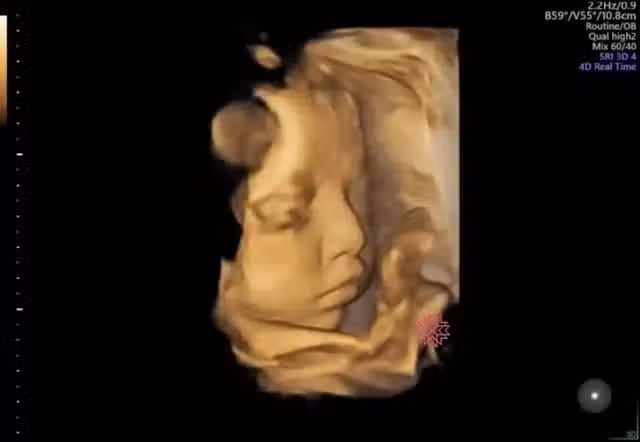

通常懷胎一段時間後,孕媽咪就開始可以感受到寶寶胎動,到了懷孕中後期胎動也會越發明顯,有時候還可能會看到孕肚鼓起來、肚皮在動~也讓人不禁好奇寶寶在子宮裡會做些什麼呢?婦產科蘇怡寧醫師就分享了一段寶寶超音波影片,畫面中寶寶竟有瞬間睜開眼睛,還露出嘟嘴微笑的表情,讓不少網友們紛紛嘖嘖稱奇、被萌了一把~

蘇醫師在臉書粉專發文,表示不少準媽咪在產檢時都會問「寶寶在肚子裡眼睛會不會打開?」因此便PO出一段4D超音波影片,證實寶寶在子宮內確實是會睜眼的,只不過睜眼的時間非常短並不容易察覺到,但蘇醫師也說寶寶睜不睜眼其實不重要,「因為你子宮內沒裝燈,眼睛打開了應該也沒什麼好看的。」